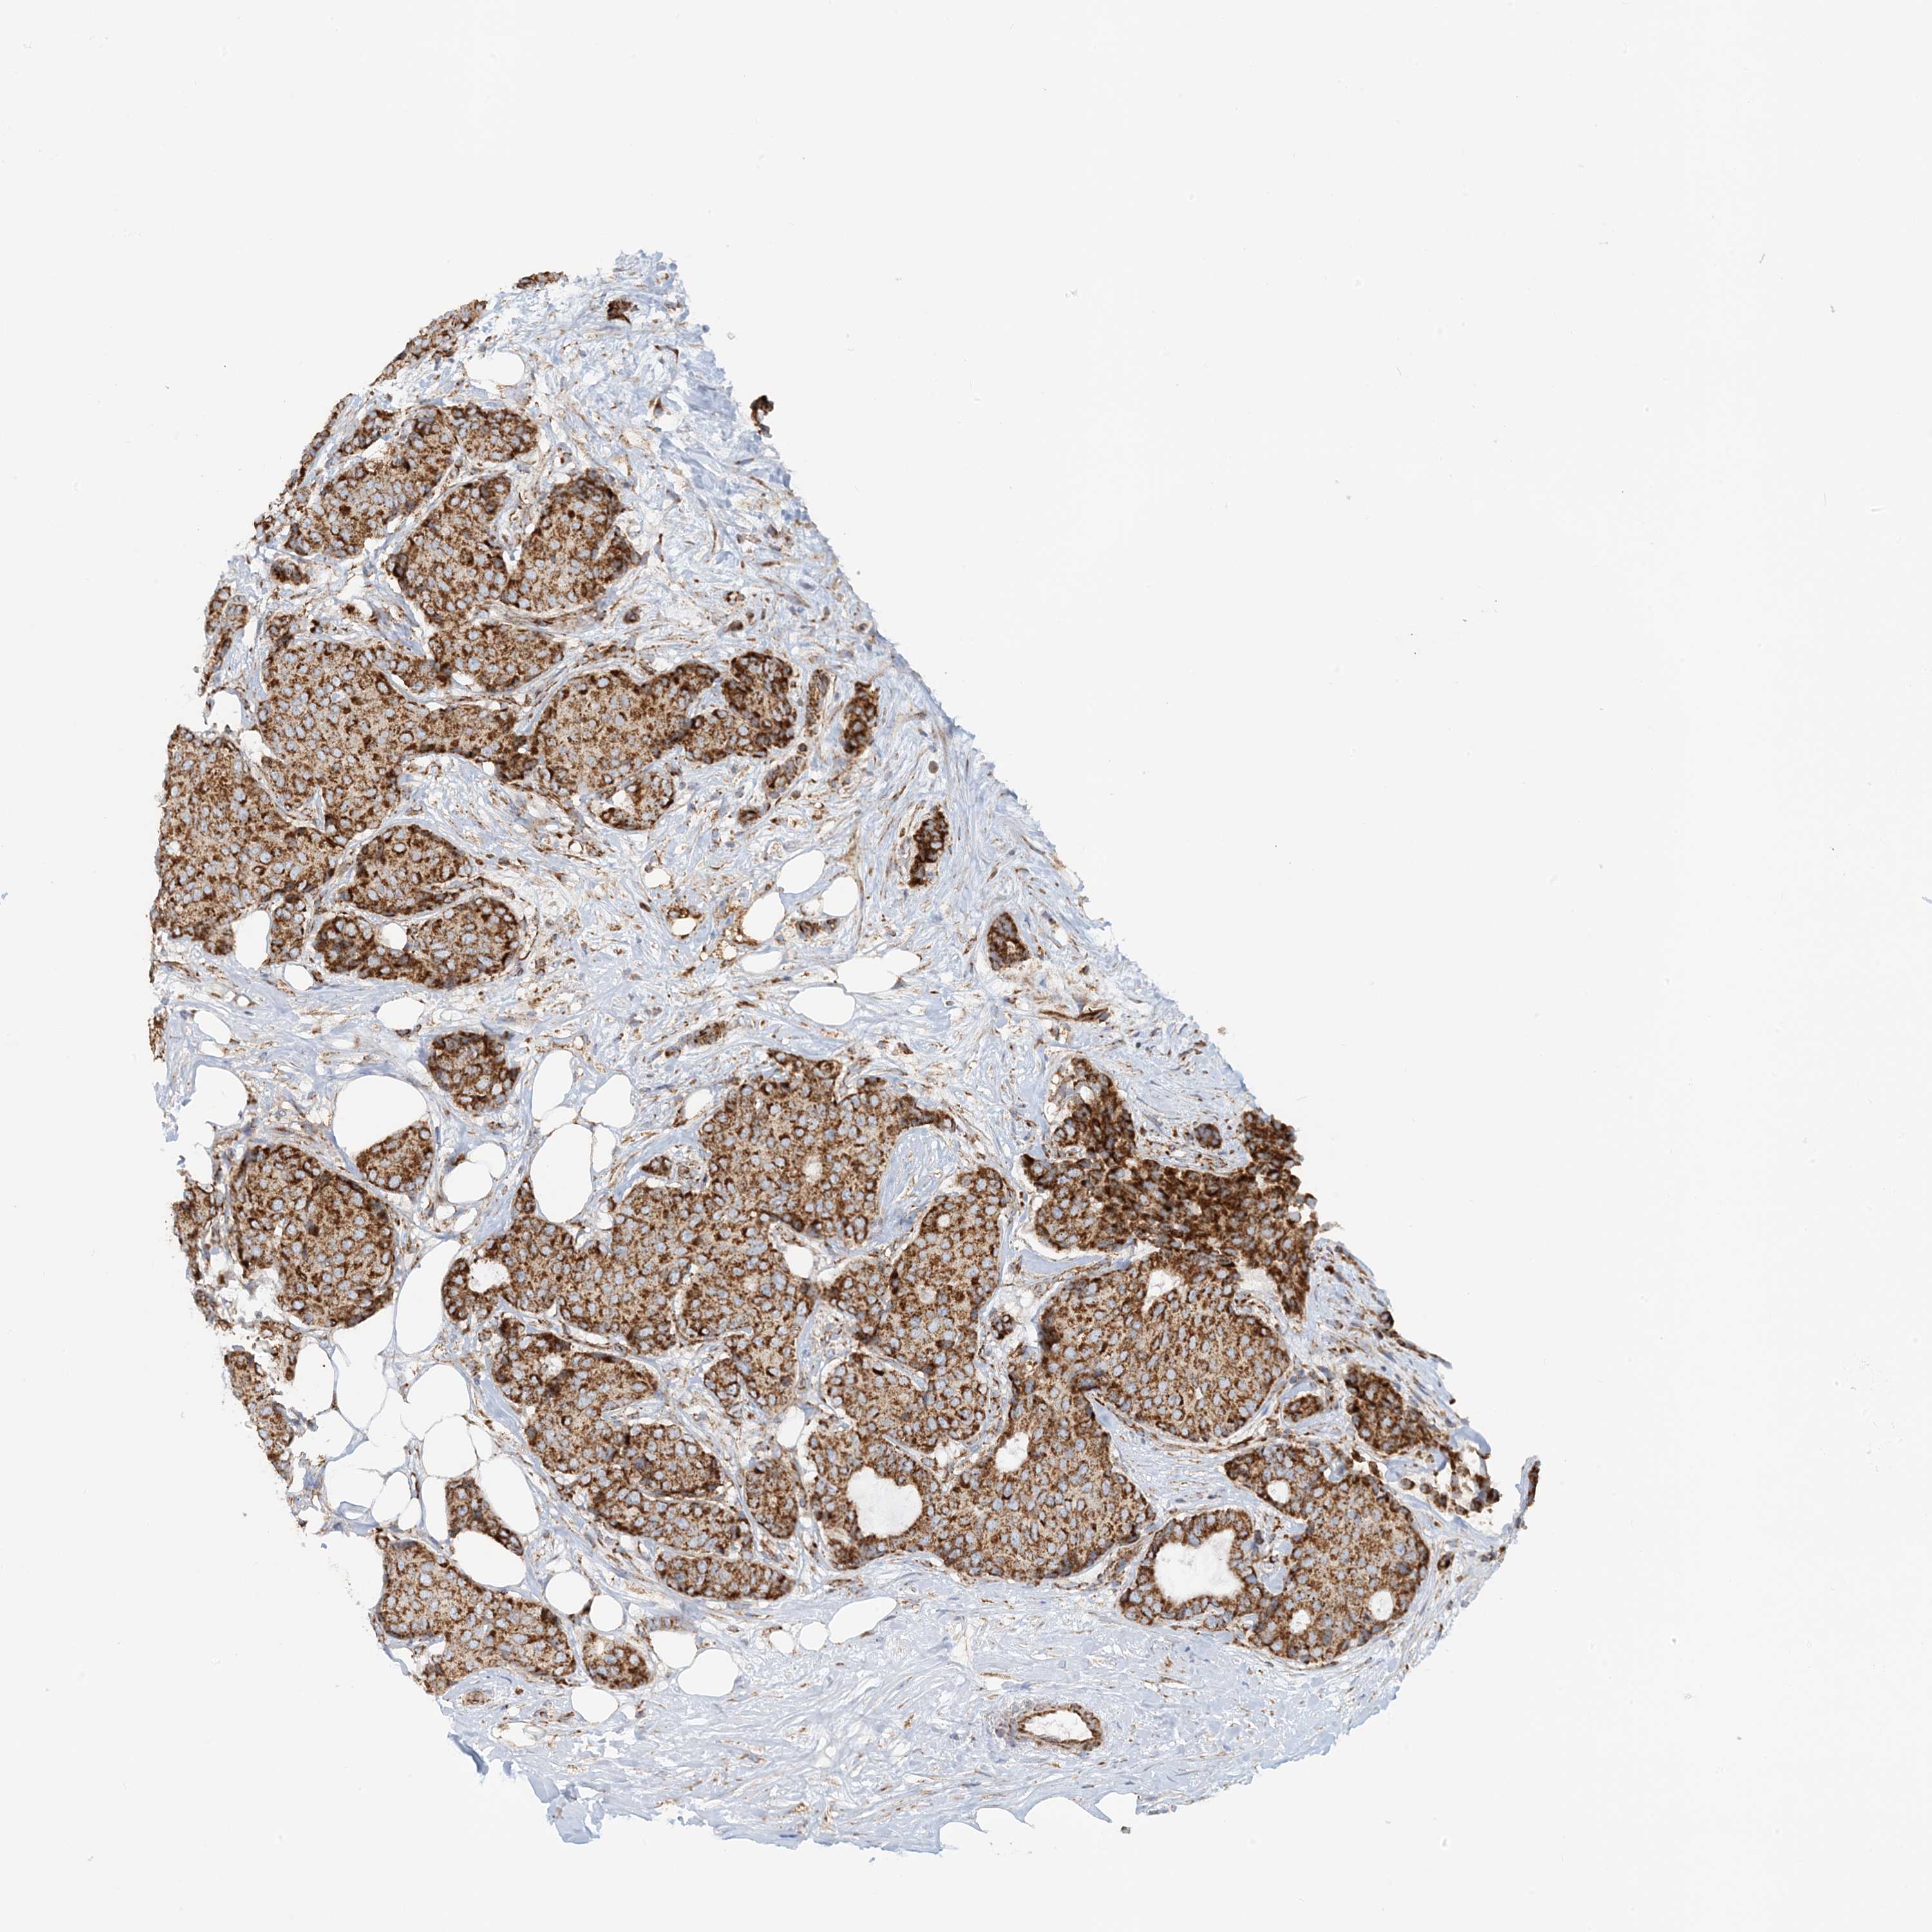

CANCER BREAST CANCER Show tissue menu

BRCA TCGA BRCA VALIDATION PROTEIN EXPRESSION

ANTIBODIES

AND

VALIDATION